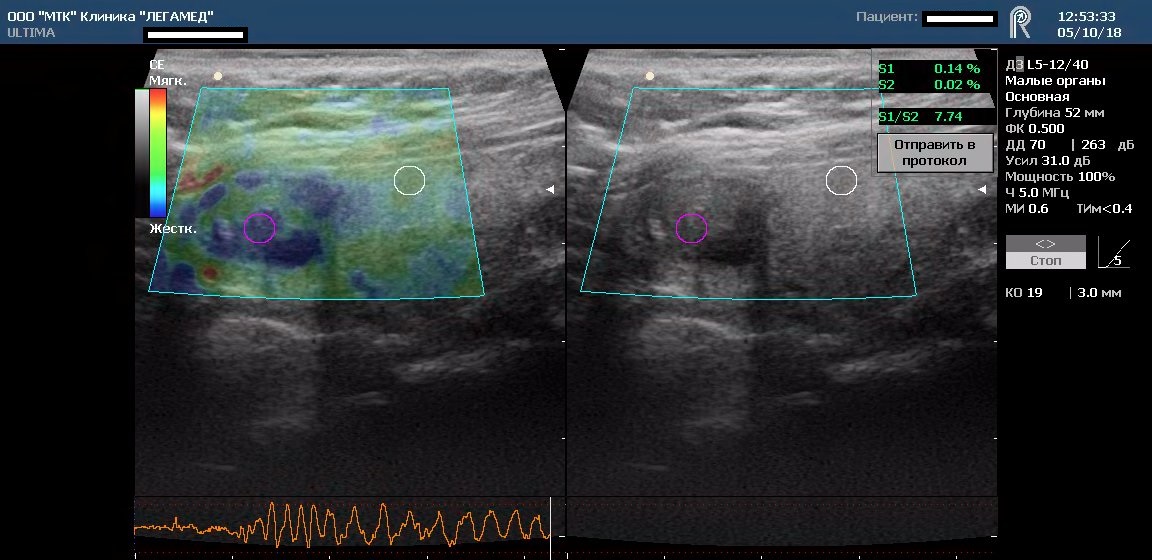

Соноэластометрия (эластография) - это передовая и перспективная  технология в УЗИ. Основной ее задачей является дифференциальная диагностика между доброкачественными и злокачественными образованиями без проведения пункции. Точность проведения диагностики данным методом доходит до 95%. По технике выполнения исследование не отличается от обычного УЗИ.

Технология соноэластометрии основана на особенностях эластичности тканей. На исследуемую ткань накладывается дополнительное давление датчиком и оценивается изменение частоты ультразвукового сигнала. Неоднородные элементы ткани вследствие неодинаковой эластичности по-разному отражают звуковую волну и окрашиваются на экране различным цветом. Кроме оценки цветовой шкалы производится измерение сопротивления тканей в "подозрительном" участке, их сравнение с окружающими тканями и точные замеры новообразования.  Таким образом, в нашей клинике врач делает заключение о наличии патологических изменений на основании точных показаний ультразвукового сканирующего диагностического комплекса экспертного класса.